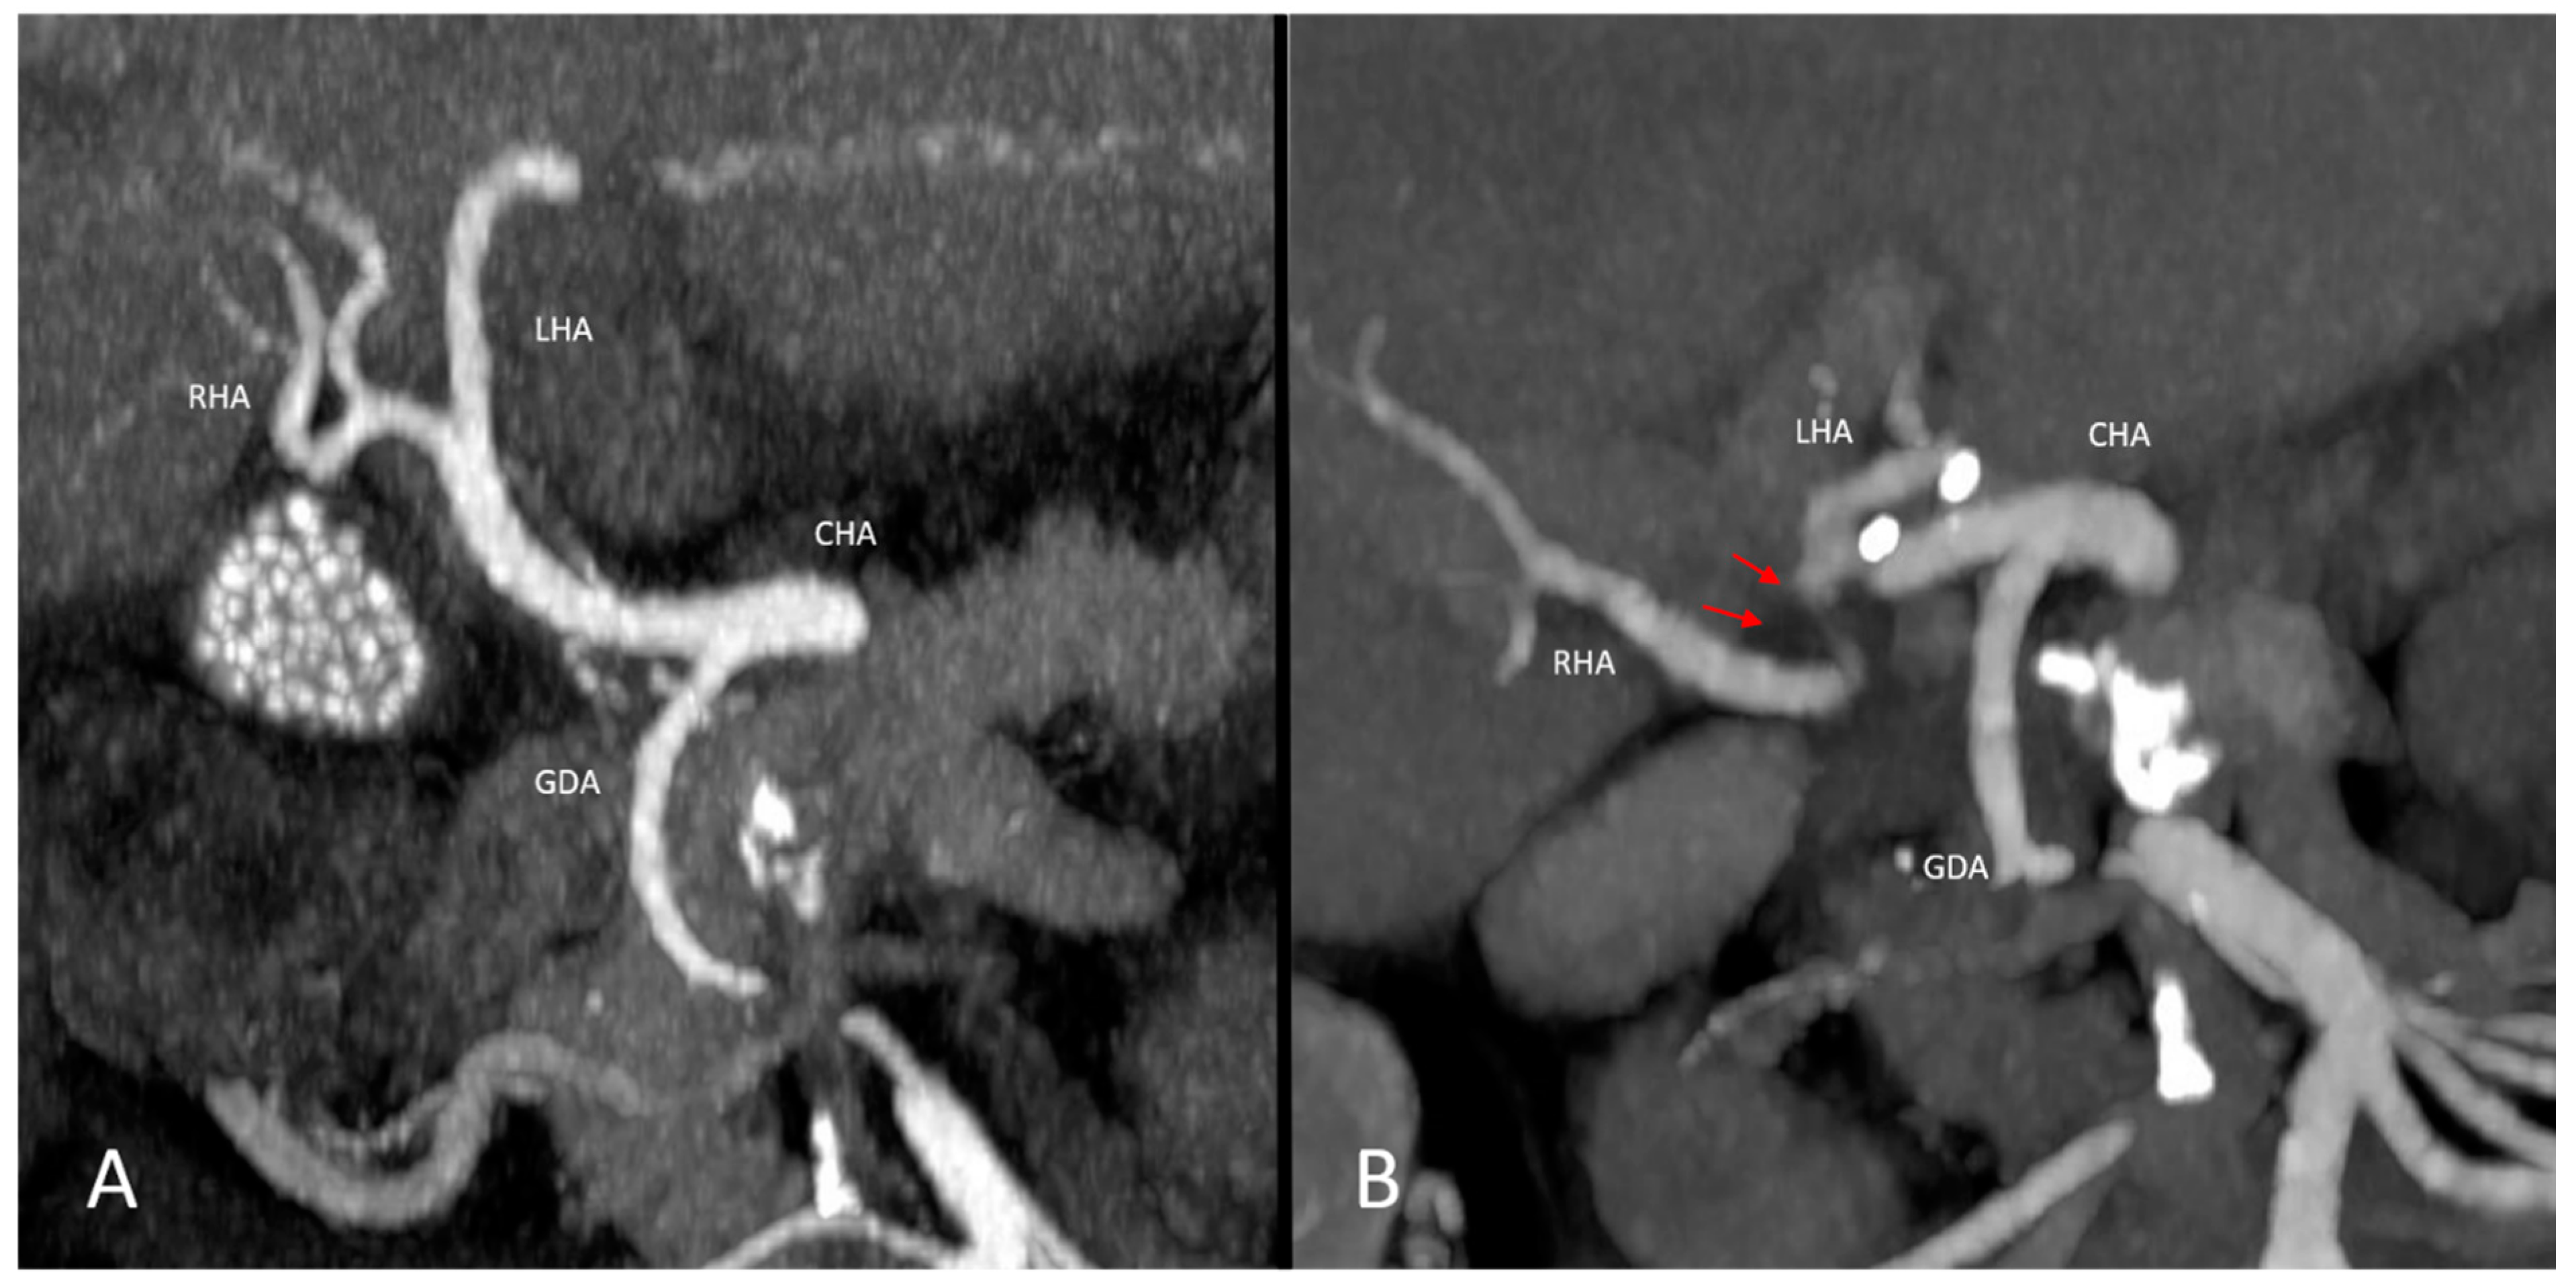

3.2. Vascular Findings—Anatomic Variants and Pre-Existing Pathologies of the Hepatic Vasculature

3.3. Analysis of Types and Occurrences of Arterial Complications